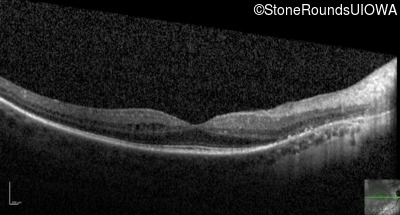

Optical Coherence Tomography - Right - 20/40 -1

Exemplar / OCT Stack